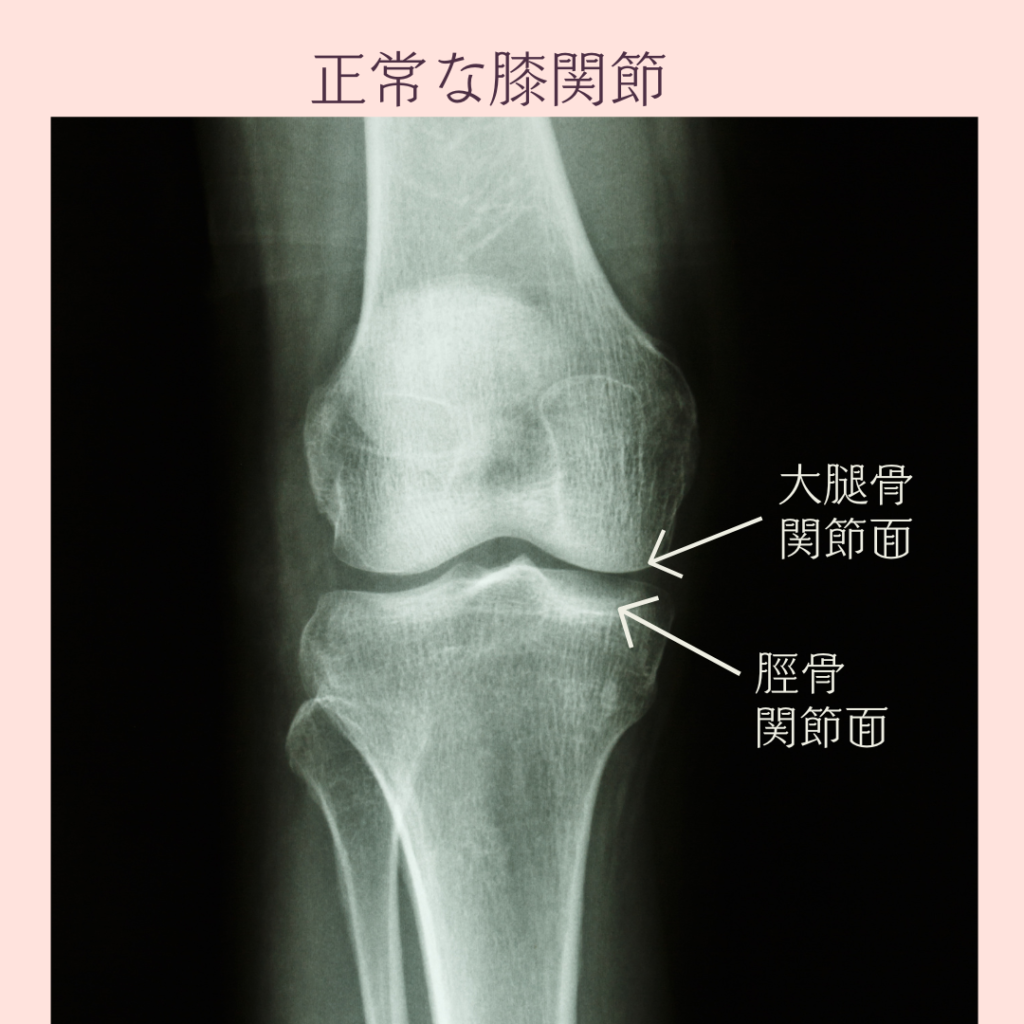

正常な膝関節は 関節のすき間が均一です

上の大腿骨の面と 下の脛骨の面が

ほぼ同じ間隔であることがで大切です

それにより、

膝の曲げ伸ばしをしたとき

面と面の全体で体重を支えることが できるのです

膝関節の中には半月板と関節軟骨があり

・大腿骨と脛骨の接合部の安定

・荷重分散

・衝撃吸収

・関節の保護

の役割があります。